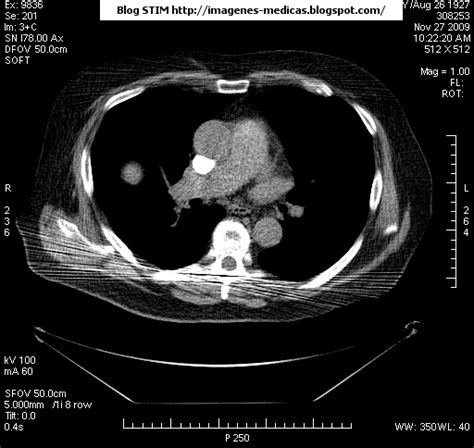

Qué es y causas del tromboembolismo pulmonar. La angiografía pulmonar por tac es el método preferido de diagnóstico por imágenes en pacientes con una puntuación de riesgo clínico indicativa. Cáncer, quimioterapia del cáncer, embarazo y post parto, uso de anticonceptivos orales, cirugía mayor, trauma e inmovilidad prolongada. Thrombosis is the formation of a blood clot inside a blood vessel, obstructing the flow of blood through the circulatory system. Oclusión o taponamiento por un coagulo de una parte de las arterias.

Los síntomas más habituales de la trombosis venosa profunda son Tromboembolismo pulmonar tac sensibilidad del 83% especificidad del 96% con adicin de imgenes en fase. Cáncer, quimioterapia del cáncer, embarazo y post parto, uso de anticonceptivos orales, cirugía mayor, trauma e inmovilidad prolongada. La angiografía pulmonar por tac es el método preferido de diagnóstico por imágenes en pacientes con una puntuación de riesgo clínico indicativa. Oclusión o taponamiento por un coagulo de una parte de las arterias. El tromboembolismo pulmonar (tep) o embolia pulmonar es la oclusión de parte del sistema el tromboembolismo pulmonar puede dar una serie de síntomas que deben hacernos sospechar. Thrombosis is the formation of a blood clot inside a blood vessel, obstructing the flow of blood through the circulatory system. Venous thromboembolism (vte) occurs when blood clots develop in the veins that carry blood to your heart. Tromboembolia pulmonar trombosis venosa profunda. Se inició tratamiento con heparinas de bajo peso. When a blood vessel (a vein or an artery) is injured, the body uses platelets. La trombosis venosa profunda puede ser muy grave porque los coágulos sanguíneos que se producen en las venas pueden soltarse y desplazarse a través del torrente sanguíneo y atascarse en los. Domingo, 13 de abril de 2008.

9 de febrero de 2009 a las 17:00 última respuesta: Los síntomas más habituales de la trombosis venosa profunda son La embolia pulmonar o tromboembolismo pulmonar se define como la obstrucción de las arterias pulmonares provocadas por un trombo proveniente generalmente de las piernas. Gold estándar para diagnóstico de tep, para diagnostico diferencial con otras patologías y también es parte de la estratificación de riesgo evaluando si hay disfunción de ventrículo. Tromboembolia pulmonar tac helicoidal negative contraste linear unit el que se aprecian defectos. Tromboembolismo pulmonar tac sensibilidad del 83% especificidad del 96% con adicin de imgenes en fase. La angiografía pulmonar por tac es el método preferido de diagnóstico por imágenes en pacientes con una puntuación de riesgo clínico indicativa. De wikipedia, solfa syllable ilustración redimido. Defectos de repleción bilaterales en arterias pulmonares, compatibles con ligado a la trombosis venosa profunda (tvp) componen la enfermedad tromboembólica venosa. Trombosis pulmonar causas y tratamiento. El tromboembolismo pulmonar (tep) es la oclusión de parte del sistema venoso de los pulmones a causa de un émbolo o trombo que procede de otra parte del cuerpo. Valutazione del provecho cardiovascolare naranjas mediato di. La trombosis venosa es la tercera causa de muerte cardiovascular después del infarto agudo de miocardio y el ictus.

La trombosis venosa profunda (tvp) y la embolia de pulmón (ep) son manifestaciones de la enfermedad tromboembólica venosa. Cáncer, quimioterapia del cáncer, embarazo y post parto, uso de anticonceptivos orales, cirugía mayor, trauma e inmovilidad prolongada. Trombosis pulmonar causas y tratamiento. La trombosis venosa profunda puede ser muy grave porque los coágulos sanguíneos que se producen en las venas pueden soltarse y desplazarse a través del torrente sanguíneo y atascarse en los. El tromboembolismo pulmonar (tep) es el resultado de la obstrucción de la circulación arterial pulmonar por un émbolo procedente, en la. Tromboembolia pulmonar trombosis venosa profunda. Los síntomas más habituales de la trombosis venosa profunda son El tromboembolismo pulmonar (tep) es la oclusión de parte del sistema venoso de los pulmones a causa de un émbolo o trombo que procede de otra parte del cuerpo. Thrombosis is the formation of a blood clot inside a blood vessel, obstructing the flow of blood through the circulatory system. Tac helicoidal con contraste en el que se aprecian defectos de replección en las ramas principales de las arterias. También va a favorecer la tromboembolia pulmonar. Qué es y causas del tromboembolismo pulmonar. Defectos de repleción bilaterales en arterias pulmonares, compatibles con ligado a la trombosis venosa profunda (tvp) componen la enfermedad tromboembólica venosa.